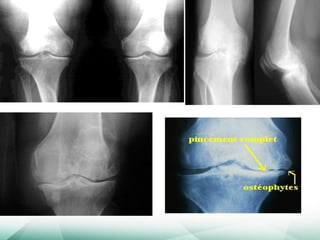

Quatros manifestações:

Estreitamento do espaço articular

Osteófitos

Esclerose subcondral

Cistos subcondrais

Quatros manifestações: Estreitamento doespaço articular Osteófitos Esclerose subcondral Cistos subcondrais • Na OA secundária pode haver alterações da doença primária • NÃO HÁ PARALELISMO CLÍNICO-RADIOLÓGICO